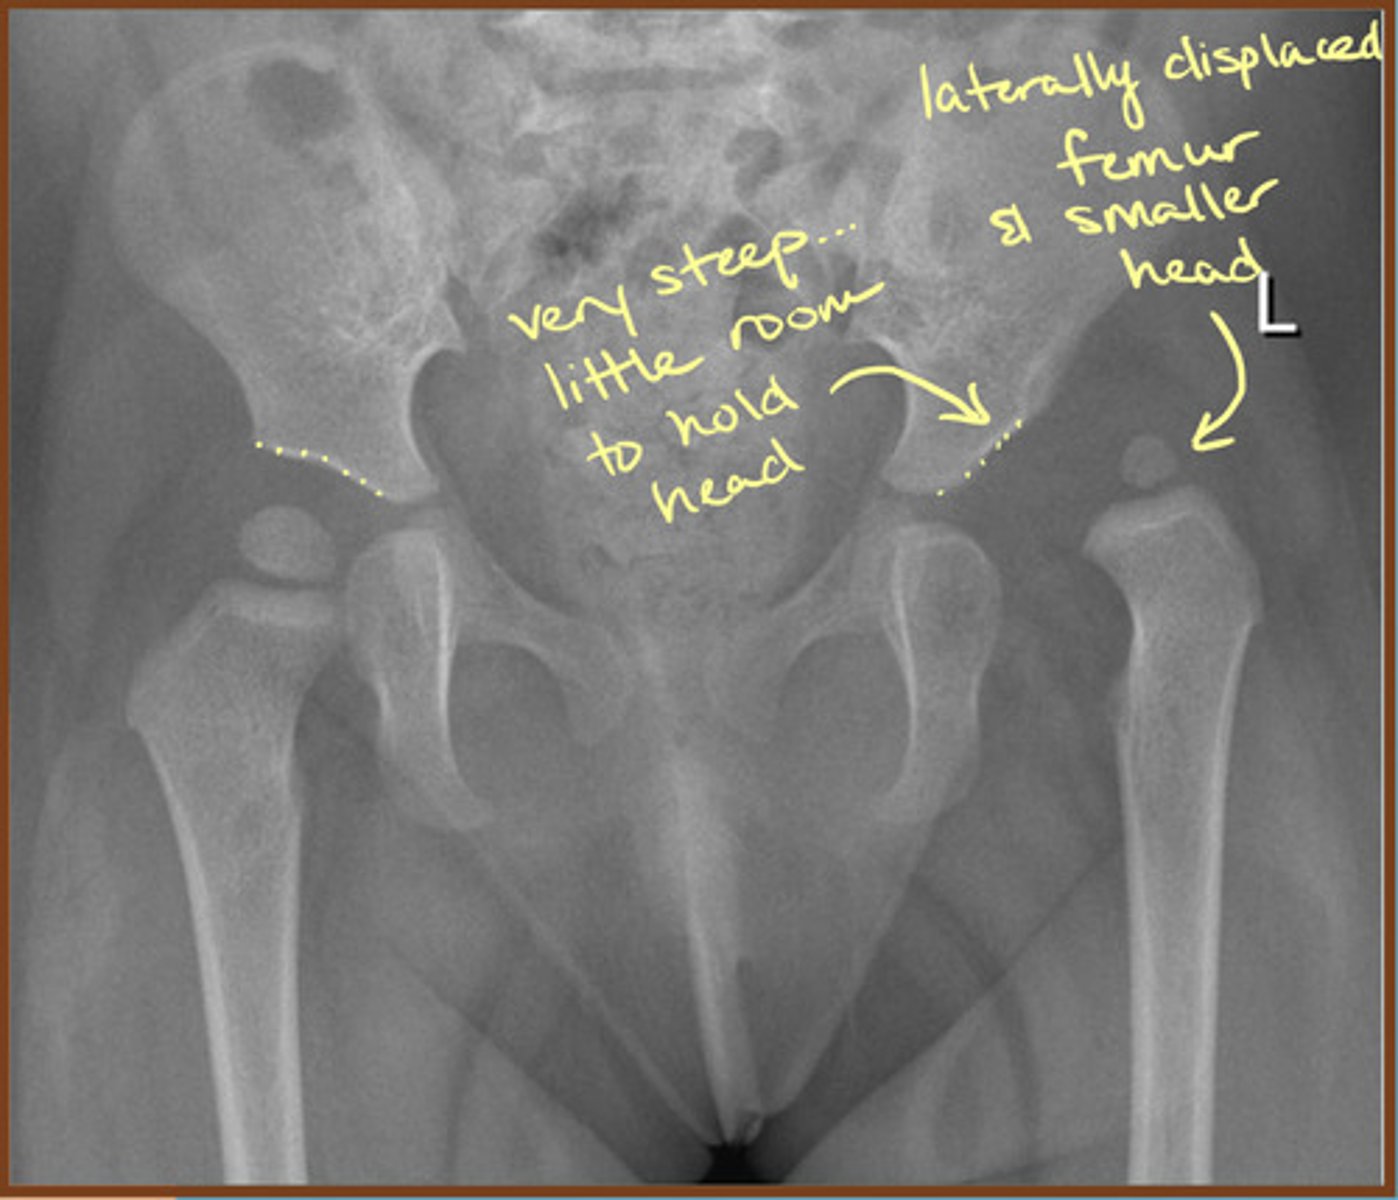

Putti's Triad

Sign of DDH

(1) Absent or small proximal femoral epiphysis

(2) Superolateral or lateral displacement of the femur

(3) Increased acetabular angle

Developmental Dysplasia of the Hip (DDH)

Aberrant development of the hip joint, resulting from an abnormal relationship of the femoral head to the acetabulum

DDH commonly causes early onset of what?

Osteoarthrosis of the hip joint (sometimes even in the teens)

DDH more frequently affects which hip?

Left hip is more frequently affected

1/3 of cases are bilateral